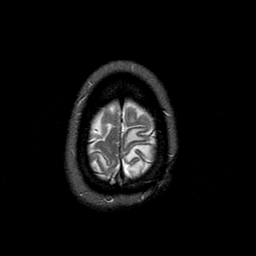

MR Study #1 -- Slice #47